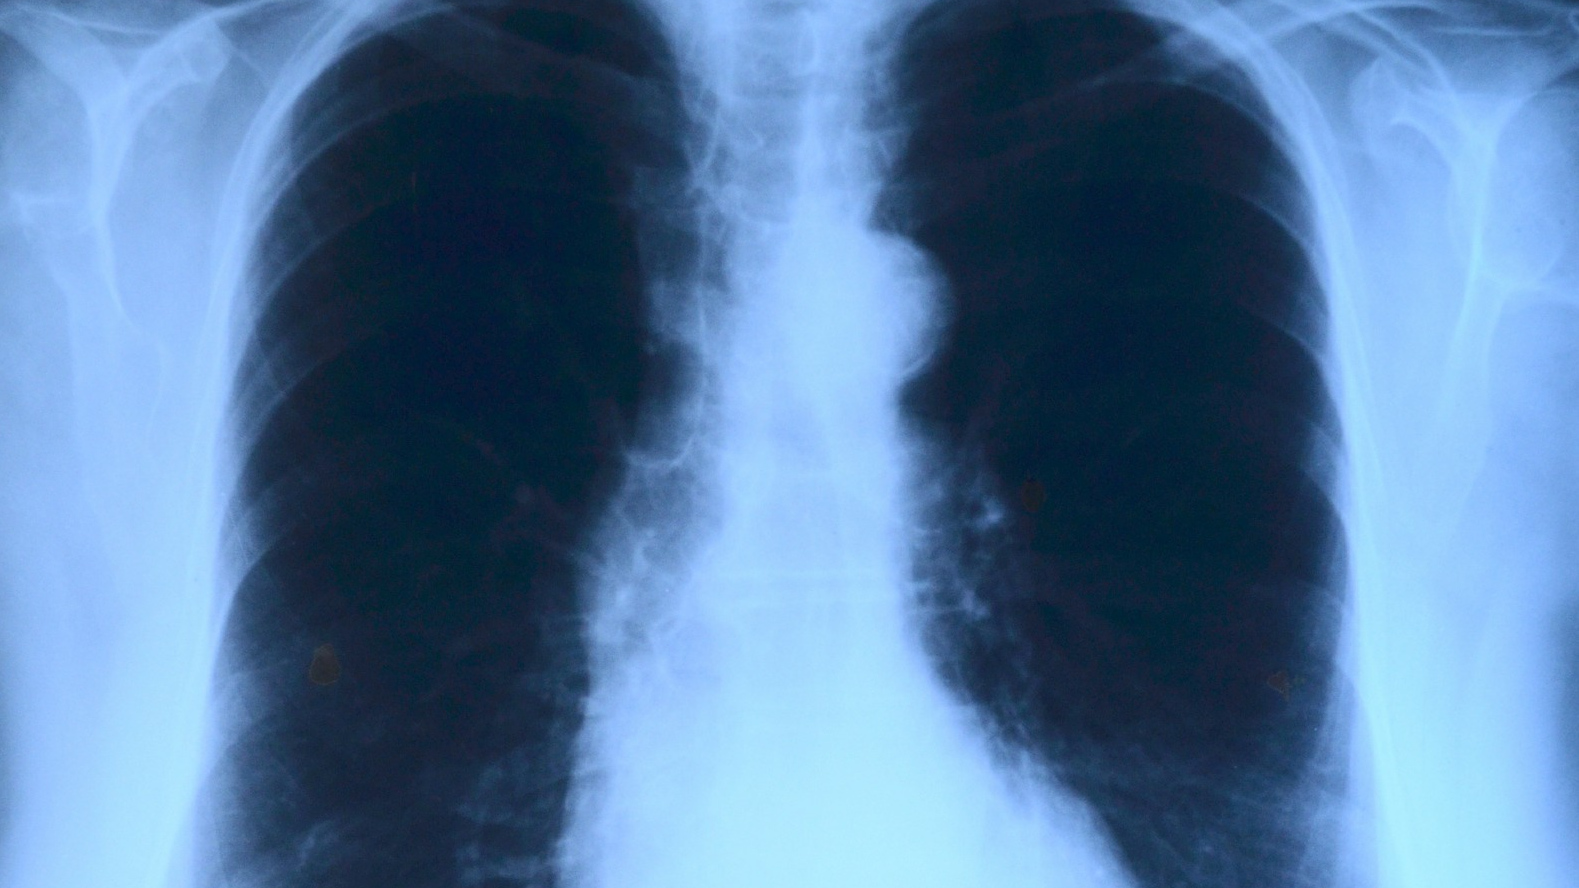

Поражение легких является одним из основных симптомов коронавируса (COVID-19). В данной статье представлены фото рентгеновских снимков, которые позволяют визуально оценить состояние легких при этом заболевании.

Хороший рентген легких

Хороший рентген легких

На фотографиях рентгеновских снимков видно, как вирус воздействует на легочную ткань. Характерные признаки поражения легких включают пятна, инфильтраты и наличие жидкости внутри легочных альвеол.

Фото рентгеновских снимков помогают врачам и специалистам визуально определить степень поражения легких и принять соответствующие меры лечения и поддержки пациента.